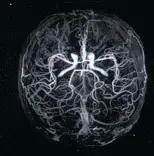

ПРИМЕРЫ ИЗОБРАЖЕНИЙ, сделанных на нашем оборудовании.

Исследование головного, спинного мозга и сосудов. Уникальные возможности оборудования позволяют визуализировать сосуды головного мозга и с высочайшей степенью достоверности, диагностировать сосудистую патологию головного мозга, включая сосудистые программы для оценки состояния мелких сосудов.